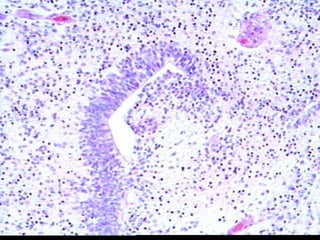

ENDODERMAL SINUS

TUMOR, aka

YOLK SAC TUMOR

ENDODERMAL SINUS TUMOR,aka YOLK SAC TUMOR